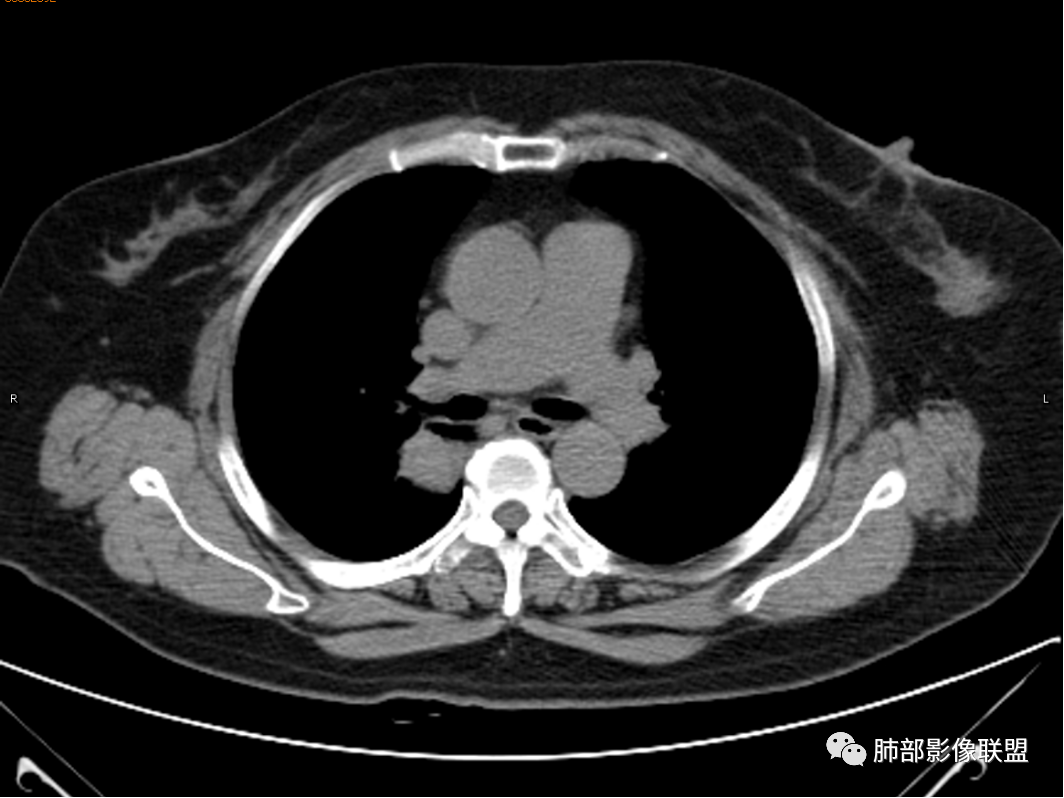

◆ 影像资料:

杨丽:老年女性,无肺气肿背景。右肺上叶后段胸膜下肿块,局部浅分叶,边缘见长软毛刺,支气管通入,临近叶间胸膜略增厚,增强扫描可见明显坏死,坏死边界清晰,壁较薄,其余病灶中等强化。纵隔小淋巴结。考虑:感染性病变,结核?鉴别囊肿伴感染。

穿越七海的风:女性,右肺上叶肺内类圆形肿物,部分边缘平直,环行强化明显,周围磨玻璃考虑出血,结核鉴别类癌。

寒江雪:椭圆形肿块,局部紧贴胸膜,软毛刺,纵隔淋巴结。强化壁薄、均匀。考虑炎性病变,结核?囊肿伴感染待排。

杨泽锋:病灶不大,坏死彻底,尽管卫星灶树芽征不明显(可能层厚太厚了),还是首先考虑TB

王武章:较为符合淋巴结结核破溃肺内浸润,主要与支气管囊肿(并感染?)鉴别

红星:咳嗽咳痰,痰中带血一个月。右肺上叶后段一个结节的阴影,分叶毛刺,肺门有淋巴结的肿大,CT值是软组织的密度。增强扫描中等程度的强化,见薄环状强化,病灶周围没有卫星病灶。首先考虑结核性的肉芽肿病变。鉴别诊断腺癌、结节病、淋巴瘤。

玫:咳嗽,咳痰,痰中带血一个月,肿瘤标志物不高,右肺上叶肿块影,边界清晰,浅分叶及少许毛刺,增强扫描病灶边缘呈环形强化,病灶内见坏死区,考虑结核可能,鉴别腺癌。

蕊:环形强化,中心性坏死,坏死界线较清楚,肺门淋巴结肿大,考虑结核可能。

薏米:咳嗽,咳痰带血就诊,右肺上叶不规则密度增高影,未见支气管截断,边缘以凹陷收缩为主,环形强化,坏死边界清,坏死比较彻底,考虑结核,鉴别鳞癌、类癌。

青藤之凉:环形强化,中心性坏死,坏死界线较清楚,肺门淋巴结肿大,考虑炎性病变,结核可能,鉴别肺癌。

王秀仙:右肺上叶后段结节,分叶,部分边缘平直部分膨隆,周围可见磨玻璃晕,密度不均,中心低密度坏死,增强薄环状强化,坏死界线较清楚,纵膈小淋巴结肿大,考虑肉芽肿性病变,结核。鉴别鳞癌。

三个石头:右肺上叶结节,平直,鹏隆都有,磨玻璃晕边界不清,坏死边界清,肺门淋巴结大。考虑炎性,结核可能。

任广国:左肺上叶后段,不规则团块,边缘有软毛刺,刀切征,增强扫描其内可见圆形坏死区,壁中等强化,纵隔内淋巴结,均匀强化,无坏死。考虑肺脓肿;鉴别:结核;

傅昌瑜:女性,咳嗽咳痰痰中带血1月。血常规、肿瘤标记物正常。CT:右上叶后段类圆形结节,内侧紧贴纵隔,前与右主支气管后壁分界不清。外后部分边缘平直收缩、矢状位可见U型凹陷、桃尖征,周围见边缘模糊的GGO,软毛刺。右上叶后段支气管似乎变狭窄。增强呈薄壁环形强化,内部强化不明显,强化时边缘似见有多个小结节与主病灶融合(芋艿子?)。远端见细小结节。整体考虑炎性病变,结核可能性大,注意鉴别腺癌。

女性,右肺上叶不规则软组织密度影,密度较均匀,边界清楚,略膨隆,增强环形强化,内壁光滑,有分隔,未见明确血管进入,考虑良性,结核?炎性肉芽肿?鉴别鳞癌。

清茶:女,咳嗽咳痰带血丝,右肺上叶见结节样肿块,边界清晰,边缘部分磨玻璃影,环状强化,内坏死区无强化,考虑恶性,鳞癌可能,鉴别结核。

右肺上叶肿块,靠近脊柱,类圆形,部分层面周围有晕,平直、凹陷、膨隆均有,水平位未见明显分叶,失状位重建有棘突/毛刺?局部叶间胸膜增厚,无明显牵拉僵硬,支气管通畅;中心无明显强化,周围环形强化影。临床:女性,亚急性病程,咳血。考虑:倾向良性,结核?

女性,咳嗽、咳痰、咯血发病,无发热,影像:右肺上叶孤立球形病灶,密度不均,周围有磨玻璃渗出,强化见环形低密度区,类癌,结核?

1.女性,咳嗽咳痰痰中带血1月。血常规、肿瘤标记物正常。             2.CT示右肺上叶不规则肿块,边缘以平直收缩为主,可见U型凹陷及桃尖征,周围见边缘模糊的GGO,软毛刺,从形态学的角度病灶更支持炎性改变; 3.增强呈薄壁环形强化,壁光整、清楚,也支持炎性改变;病灶内部平扫CT值密度比较高,约40HU,明显高于水的密度,而且未见强化,提示病灶的坏死可能为凝固性坏死;    4.从上面的分析,病变更符合炎性,患者白细胞不高,治疗后没有好转,不支持普通细菌的感染;影像病灶较局限,边界较清楚,病灶慢性炎症或肉芽肿,形态机发病部位更符合继发性肺结核。患者非易感人群,病灶孤立,尽管有液化,也很难第一时间考虑真菌,尤其是曲霉菌感染。什么是炎性肉芽肿?炎性肉芽肿的常见疾病谱系有哪些?那什么是凝固性坏死和干酪样坏死?跟一般的液化性坏死有什么区别?接下来我们逐一学习一下。